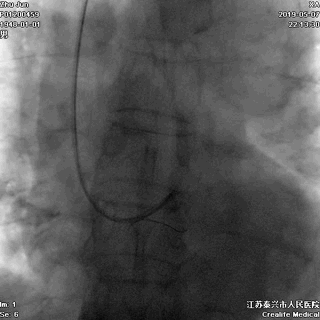

游离一根导丝至升主动脉,防止导管深插

轻轻冒烟,证实指引导管到位

轻轻冒烟,大致了解前降支的情况

这一步相当重要。否则,无论是导管嵌顿,还是导管深插,稍不留意患者都有可能一招致命。